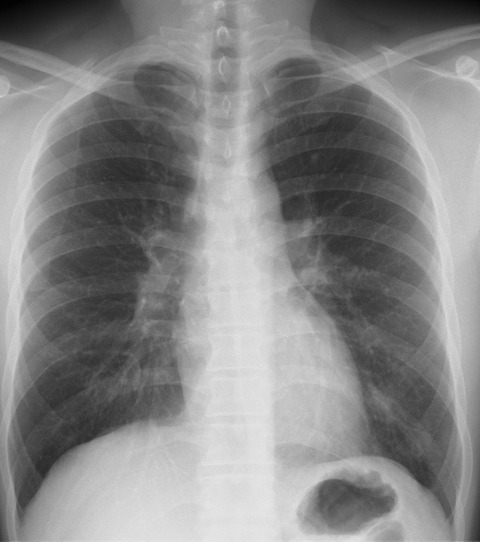

インフルエンザA肺炎50歳